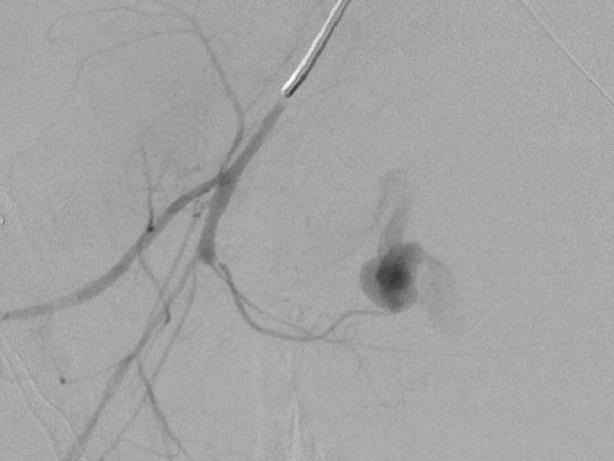

胰十二指肠上、下动脉瘤(sandwich 技术+瘤囊填塞技术)

肠系膜上动脉造影显示胰十二指肠上动脉后弓及前弓各有动脉瘤 |

选择性第一空肠动脉造影显示胰十二指肠下动脉起自第一空肠动脉,其起始部见假性动脉瘤 |

微导管经瘤腔释放微弹簧圈阻塞动脉瘤远端胰十二指肠下动脉前弓,避免侧支动脉充盈动脉瘤 |

阻断动脉瘤远端后同时进行动脉瘤内填塞 |

肠系膜上动脉胰十二指肠下动脉另一分支造影显示其起始部动脉瘤 |

动脉瘤囊内微弹簧栓子填塞 |

填塞后 |

术后动脉造影 |